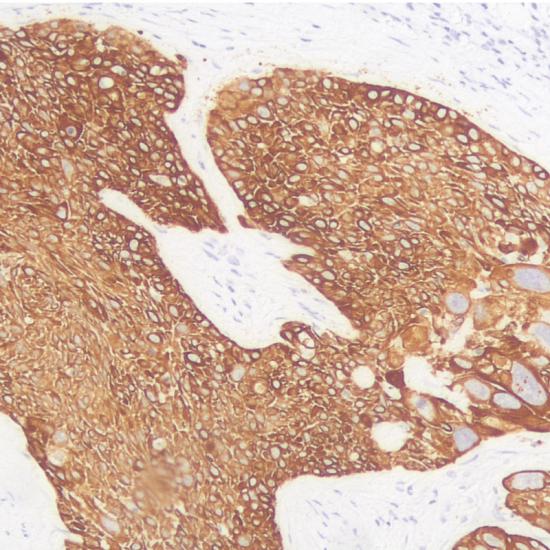

CK14

CK14屬于酸性角蛋白。在乳腺腺體和導(dǎo)管肌上皮細(xì)胞、唾液腺腺泡和導(dǎo)管的肌上皮細(xì)胞以及鱗狀上皮的基底細(xì)胞中陽性表達(dá)。大多數(shù)鱗狀細(xì)胞癌表達(dá)陽性,并且陽性表達(dá)的頻率與其分化程度無明顯關(guān)系。主要用于鱗狀細(xì)胞癌的診斷,尤其是低分化鱗癌的診斷。